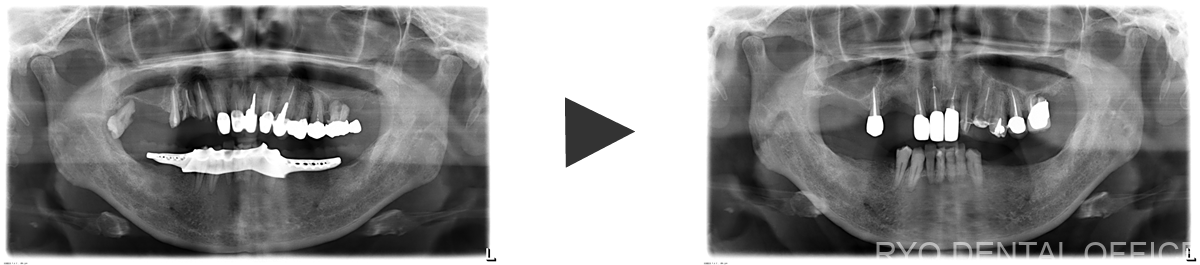

当院に初めてご来院いただ時点で右上のブリッジがボロボロでした。

そのため、噛み合わせの再構築から始めた患者様です。

所々根管治療も上手くいっていなかったため、全て顕微鏡根管治療を施しました。

治療前後のレントゲン画像